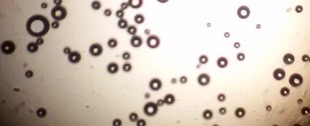

Proniosomes were transformed to noisome by hydrating with 10 ml distilled water at 37 °C and gentle agitation using vortex mixer (MaxiMix II, USA) for 5 min. The formed niosomes were sonicated twice for 30 seconds using sonicator (SONICS VCX 130, USA) [25]. The niosomal dispersion was put on a glass slide, and the formed vesicles were observed at a magnification of 1000x through an optical microscope. The formation of vesicles was observed using an optical microscope and photomicrographs were recorded [26].

The optical photographs of all reconstituted proniosomal formulae are shown in fig. (1-28). The photographs revealed that the formed niosomes are unilamellar vesicles with a spherical shape and smooth surface. The vesicles were insular and separate without aggregation or lumping. Apparently, proniosomal formulae containing span 40 and span 60 yielded vesicles of large numbers with well-identified outline and core which will affect the entrapment efficiency of loaded drug directly. However proniosomal formulae containing span 20 and span 80 produced small numbers of vesicles with a slightly different outline. This may be due to the high phase transition temperatures of both span 40 and span 60 which will cause the formation of a large number of stable niosomal vesicles. The phase transition temperatures for span 20, 40 and 60 are 16, 42 and 53 °C; respectively, however, span 80 possess the lowest phase transition temperature at 12 °C [35]. This explains why proniosomal formulae containing span 20 and span 80 produce small numbers of vesicles upon hydration.